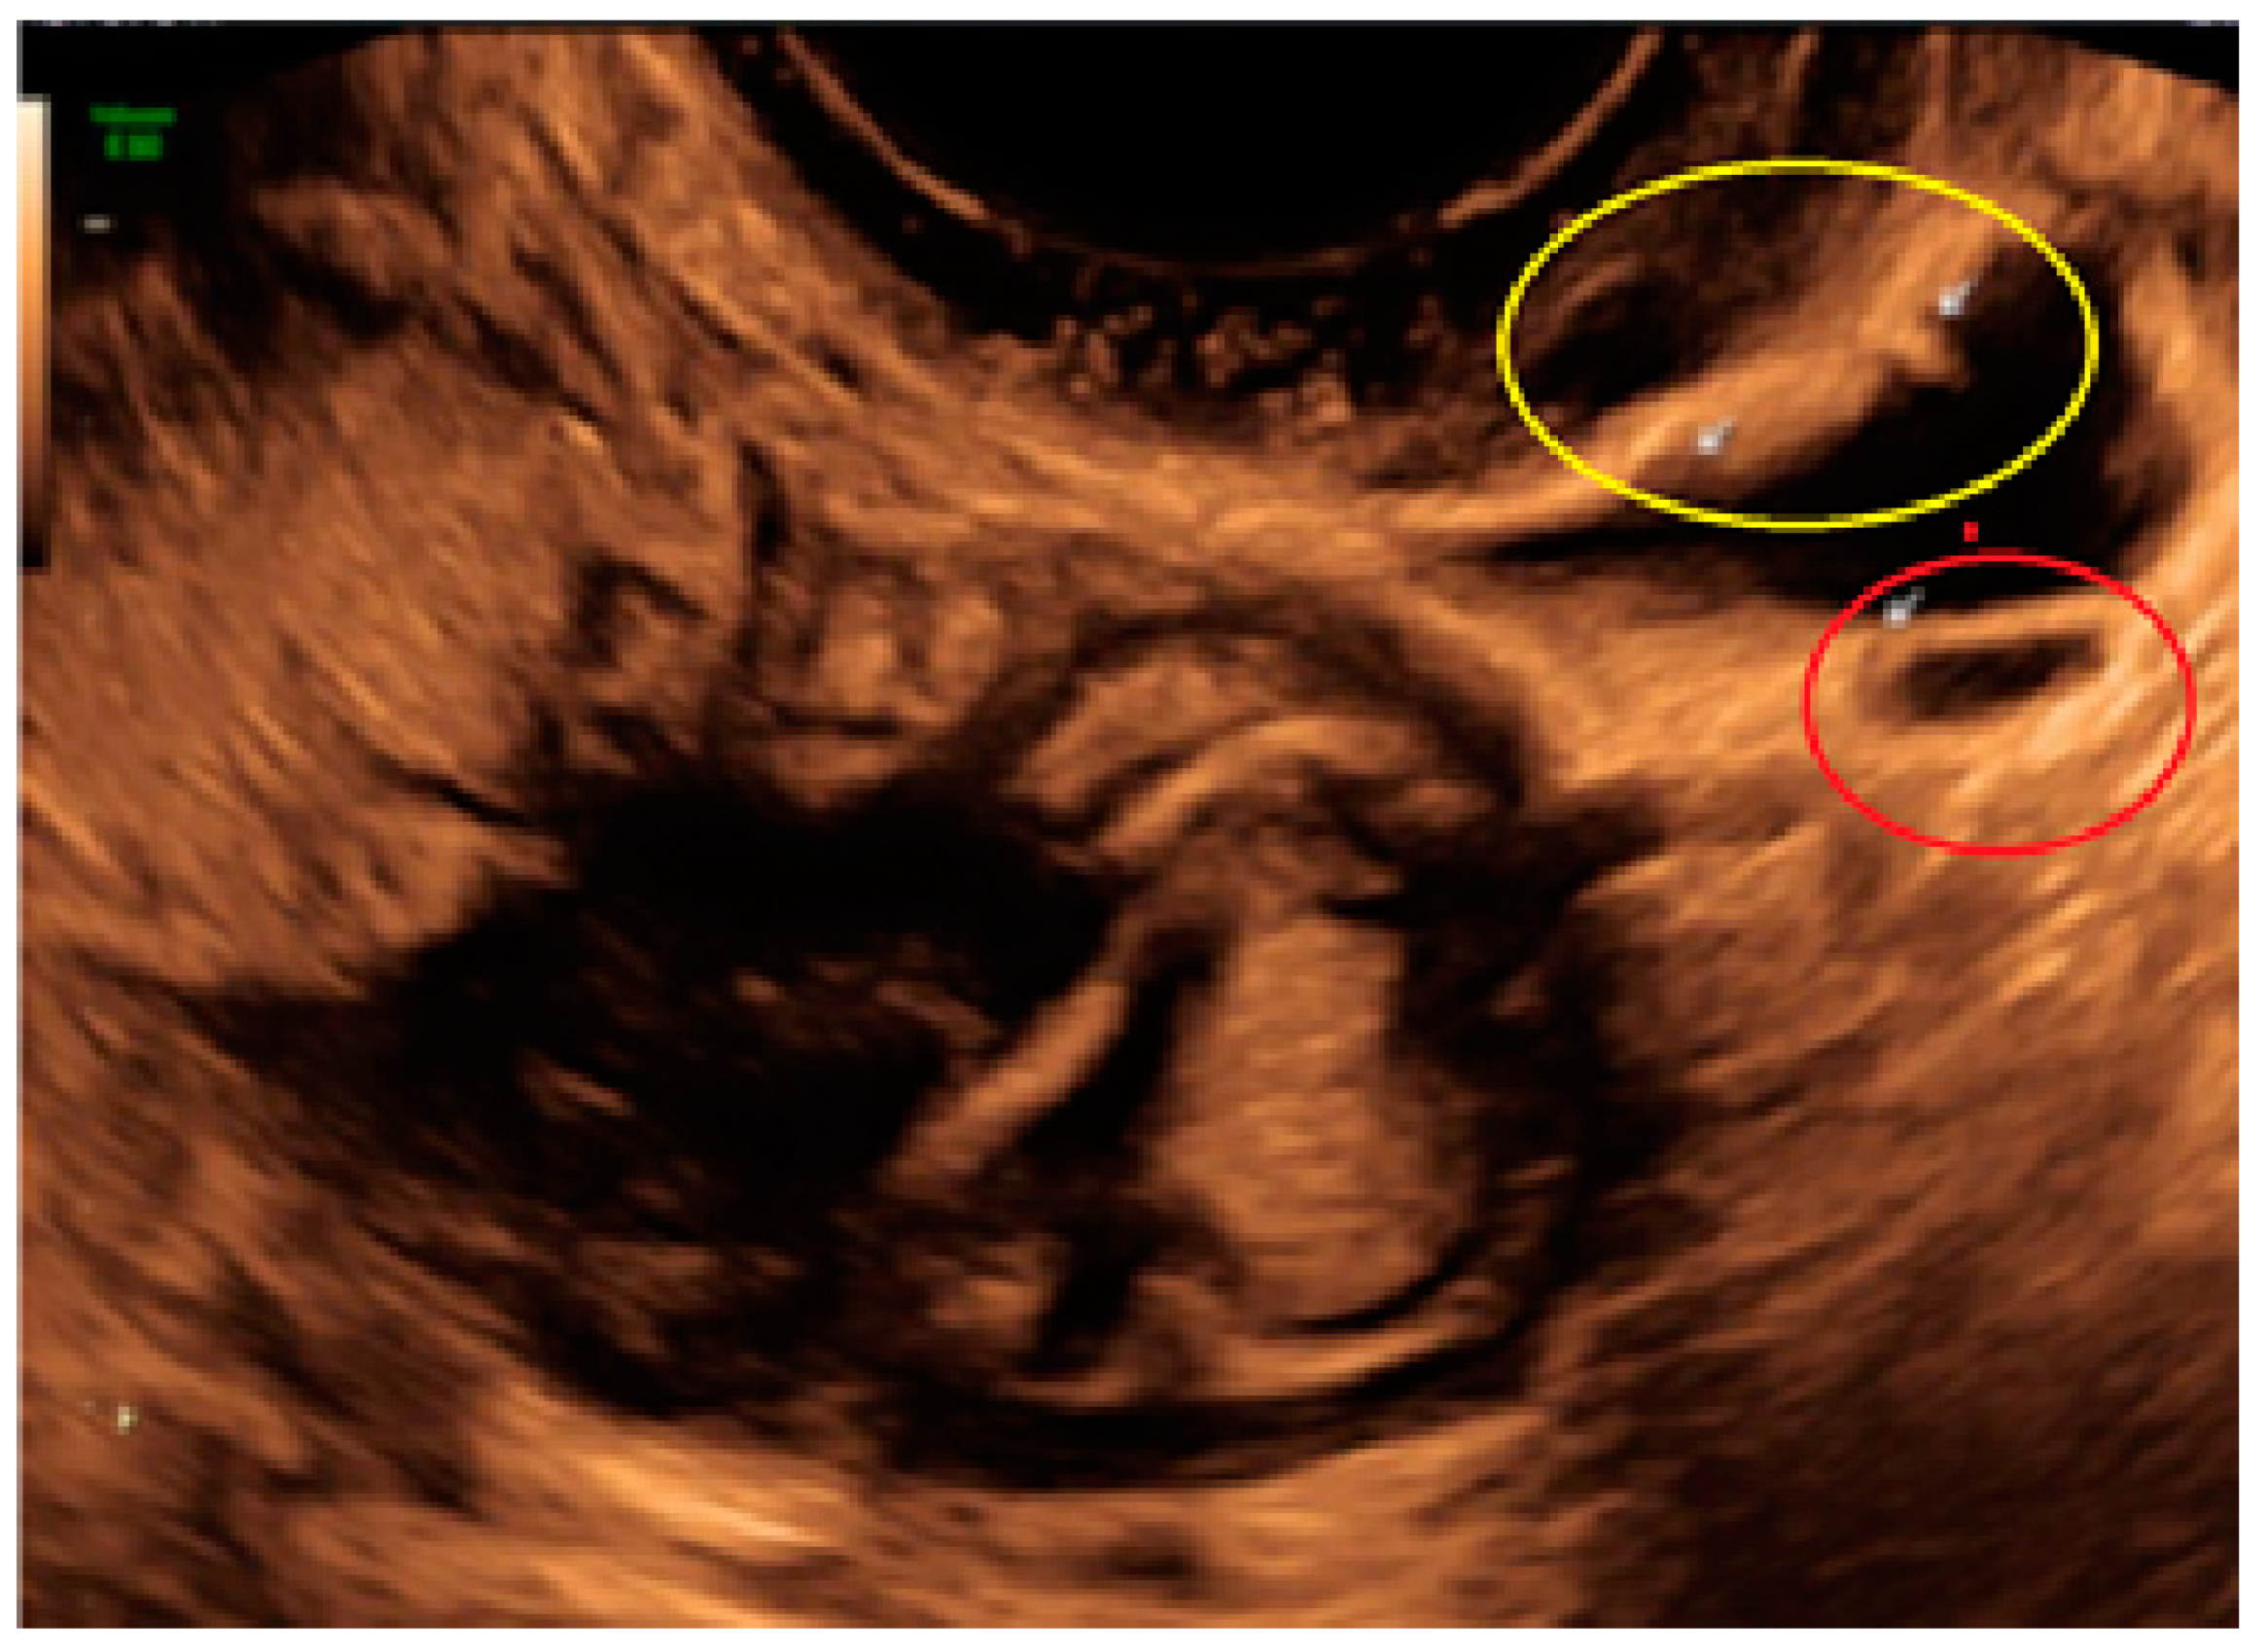

- The presence of hypoechogenic associated tissue (hypoechoic areas surrounding a small cyst area; we called this a “hat”). This tissue does not protrude or invaginate the peritoneal surface.

- The lesion may be convex, protruding from the peritoneal surface into the peritoneal cavity (we called this “bulging”), or it may appear as a concave defect in the peritoneum (we called this a “pocket”).

- The presence of hyperechoic foci (we called this a “pearl”).

- The presence of velamentous (filmy) adhesions associated to the lesion (we called this a “veil”).